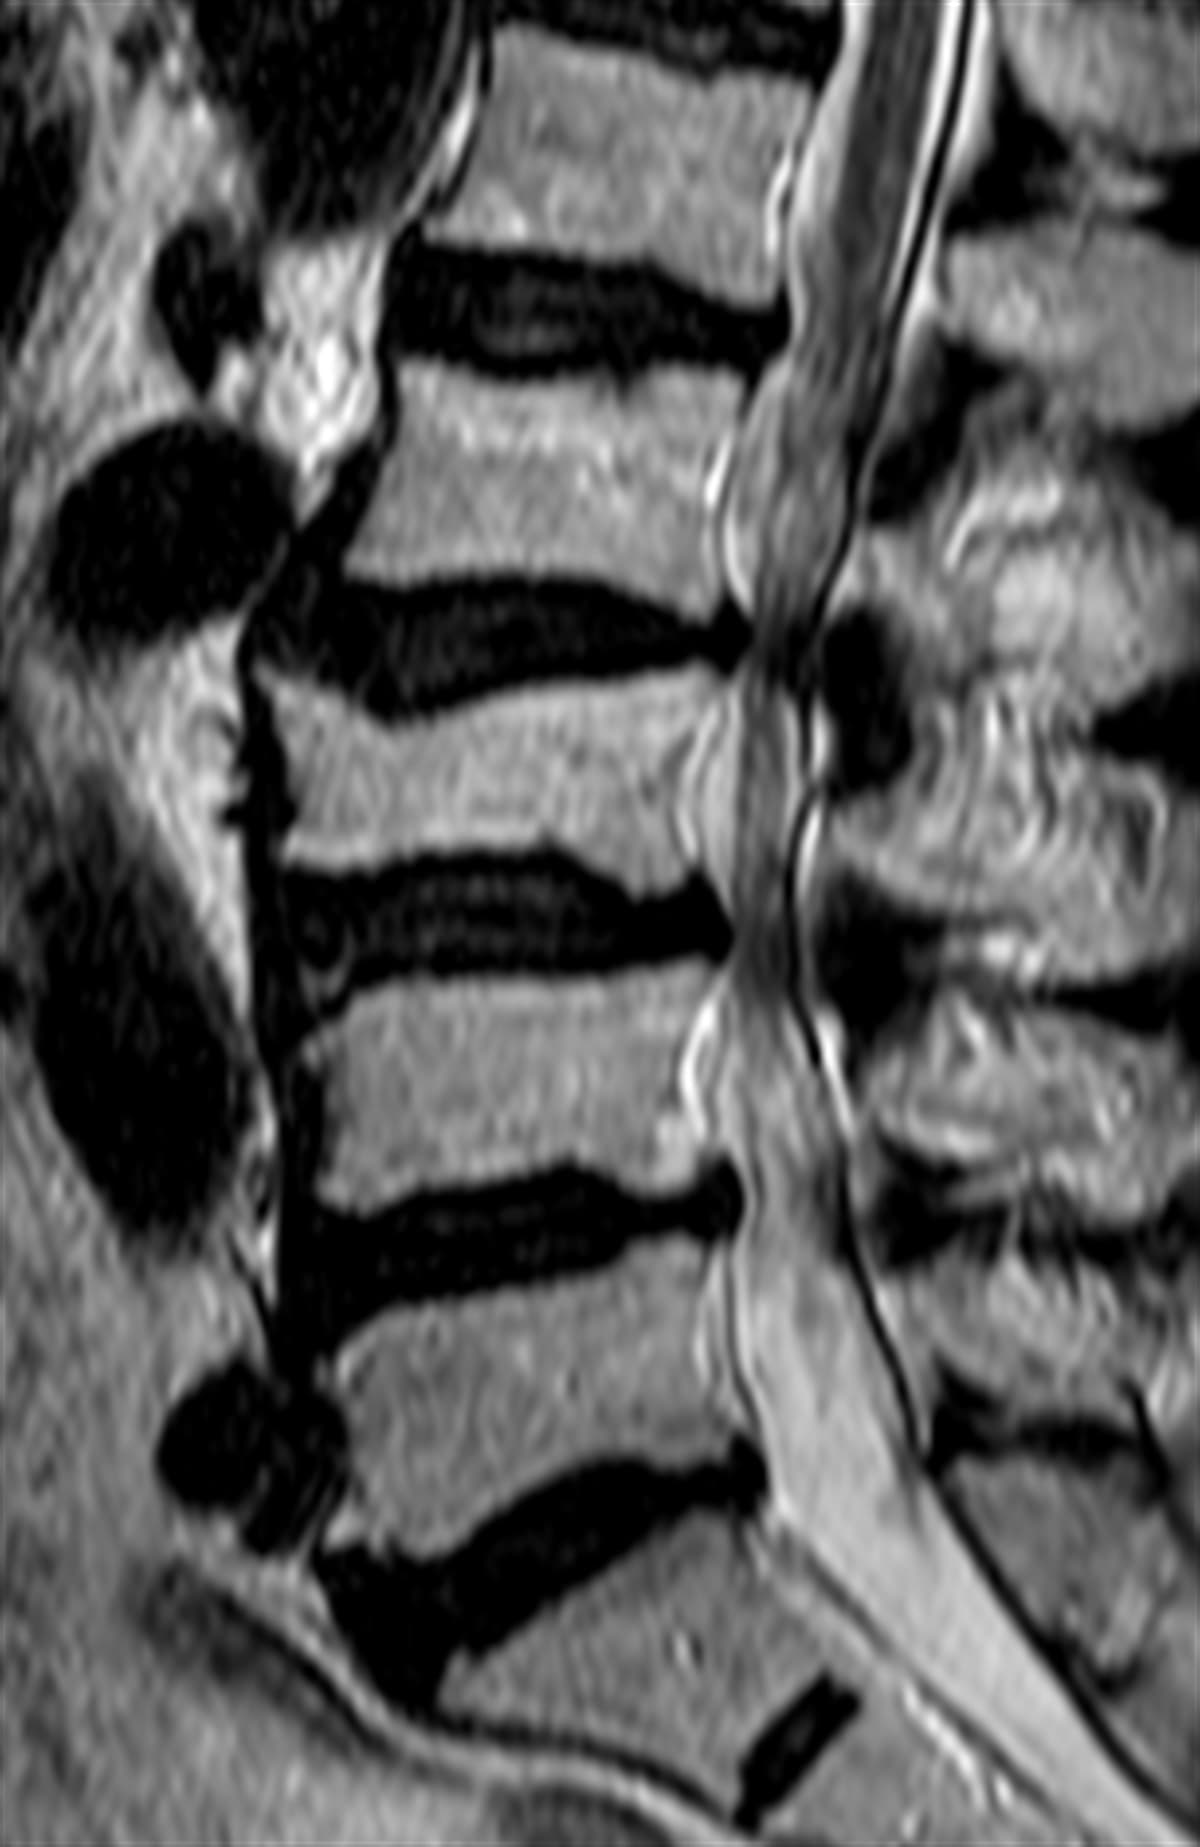

Lomber (bel) kanal darlığı nedir?

Lomber kanal darlığı, omurilik kanalının veya sinirlerin ve diğer yapıların o kanalla iletişim kurduğu tünellerin daralmasıdır. Omurga kanalının daralması genellikle, omurlardan birinin hizanın dışına çıkması da dahil olmak üzere kanalın boyutunu azaltan yaşlanma ile ilişkili değişiklikler nedeniyle oluşur.

Omurilik kanalının veya sinirleri koruyan yan kanalların daralması, genellikle omuriliğin sinir kökünün sıkışmasına neden olur. Kanalın çapı daraldıkça sinirler giderek daha fazla tahriş olur.